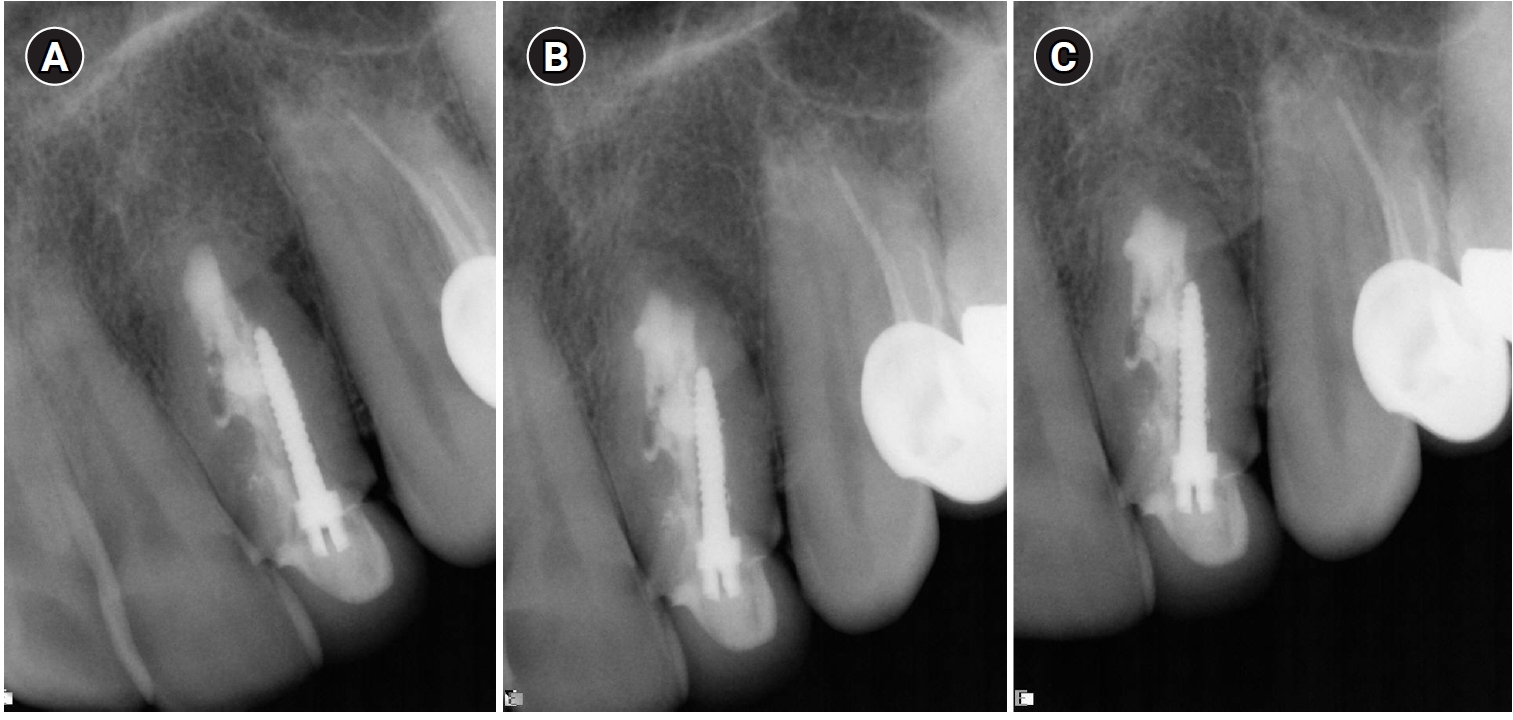

A 13-year-old girl was referred to the endodontic department in 1972, with a diagnosis of DI, pulp necrosis, and a chronic apical abscess in the left lateral maxillary incisor. Nonsurgical root canal treatment (NSRCT) was performed over three visits as described in a previous case report [16]. At the third visit, the tooth was asymptomatic and was obturated with gutta-percha and AH26 cement (DeTrey, Zurich, Switzerland) using the lateral condensation technique. A radiograph taken two years later showed evidence of healing of the periapical radiolucency (Figure 1), and complete healing was observed at the 3-year follow-up, as documented in the case report by Tagger [16].

Nonsurgical root canal treatment on tooth #22. (A) Preoperative radiograph in 1972 showing a periapical radiolucent area that extends mostly on the distal surface of the root. Note: an access cavity was present. Gutta-percha cone inserted in the sinus tract leading to the sulcus of the tooth. Three pulp cavities are visible: the distal one exposed by the access cavity, the middle one partly lined with enamel, and the mesial one is closed and present only in the apical half of the root. (B) Postoperative radiograph in 1972. Note the extruded cement and gutta-percha point beyond the apex. Mesial cavity unfilled. (C) Two-year follow-up radiograph in 1974 showing a decrease in the size of periapical radiolucency. Excess filling material settled on the distal aspect of the root. Reprinted from the article of Tagger et al. [16] with the permission of Elsevier.

Figure 1. Nonsurgical root canal treatment on tooth #22. (A) Preoperative radiograph in 1972 showing a periapical radiolucent area that extends mostly on the distal surface of the root. Note: an access cavity was present. Gutta-percha cone inserted in the sinus tract leading to the sulcus of the tooth. Three pulp cavities are visible: the distal one exposed by the access cavity, the middle one partly lined with enamel, and the mesial one is closed and present only in the apical half of the root. (B) Postoperative radiograph in 1972. Note the extruded cement and gutta-percha point beyond the apex. Mesial cavity unfilled. (C) Two-year follow-up radiograph in 1974 showing a decrease in the size of periapical radiolucency. Excess filling material settled on the distal aspect of the root. Reprinted from the article of Tagger et al. [16] with the permission of Elsevier.